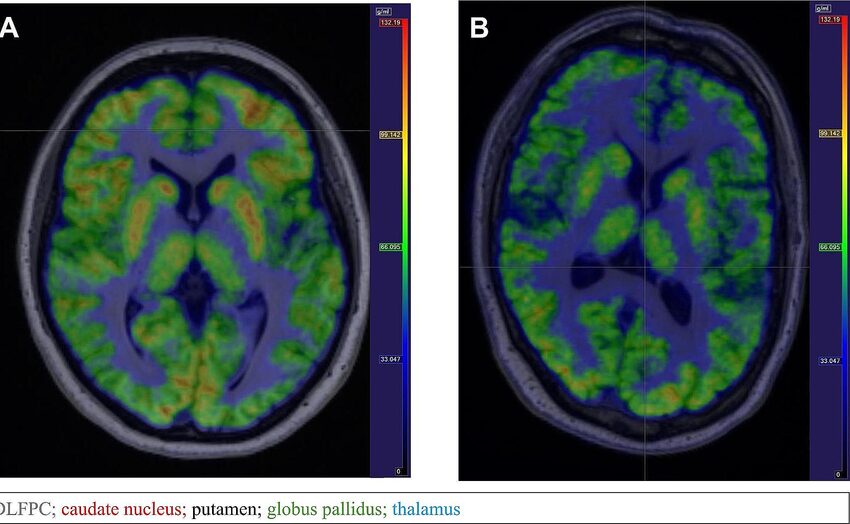

⑥ fMRI(機能的MRI)1990年代

原理

血中酸素濃度(BOLD信号)を測定。

可能になった研究

- 感情

- 記憶

- 意識

の脳活動を可視化。

意義

認知神経科学の中心技術になりました。